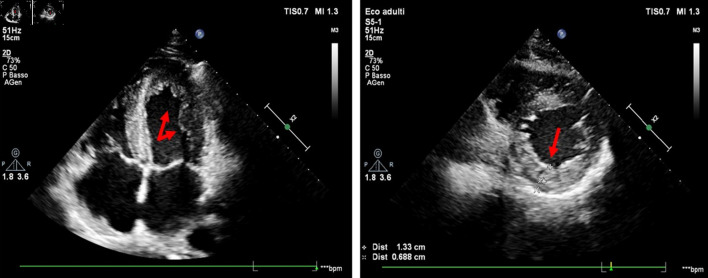

Left ventricular non-compaction (LVNC) is a rare primary cardiomyopathy with genetic etiology, resulting from an abnormality of myocardial development during embryogenesis. It carries an elevated risk of left ventricular dysfunction, thromboembolic events and malignant arrhythmias. We report the case of LVNC associated with paroxysmal atrial fibrillation and ankyrin 2 (ANK2) mutation at the genetic test. An 18-year-old competitive athlete visited our medical center to undergo the diagnostic investigations protocol preparatory to the release of the suitability for competitive practice. The echocardiographic examination shows LVNC without ventricular remodeling (left ventricular ejection fraction (LVEF) 53%, global longitudinal strain (GLS) -18.3%). The echocardiographic diagnosis was confirmed by cardiac magnetic resonance imaging (cMRI), which revealed dense hypertrabeculation in the left ventricular apex and lateral wall. The cardiogenetic investigation showed a c.9145C>T variant (p.Arg3049Trp) identified in the ANK2 gene. This mutation is associated in the literature with rare cases of LVNC. The patient underwent an extended Holter monitoring which excluded ventricular arrhythmic events but showed two brief episodes of paroxysmal atrial fibrillation. Despite the absence of significant ventricular remodeling, considering the presence of paroxysmal atrial fibrillation and the presence of a mutation in the ANK2 gene, which has several variants related to high-risk phenotypes, it has been decided to suspend the competitive practice, and is defined an adequate clinical-diagnostic follow-up.